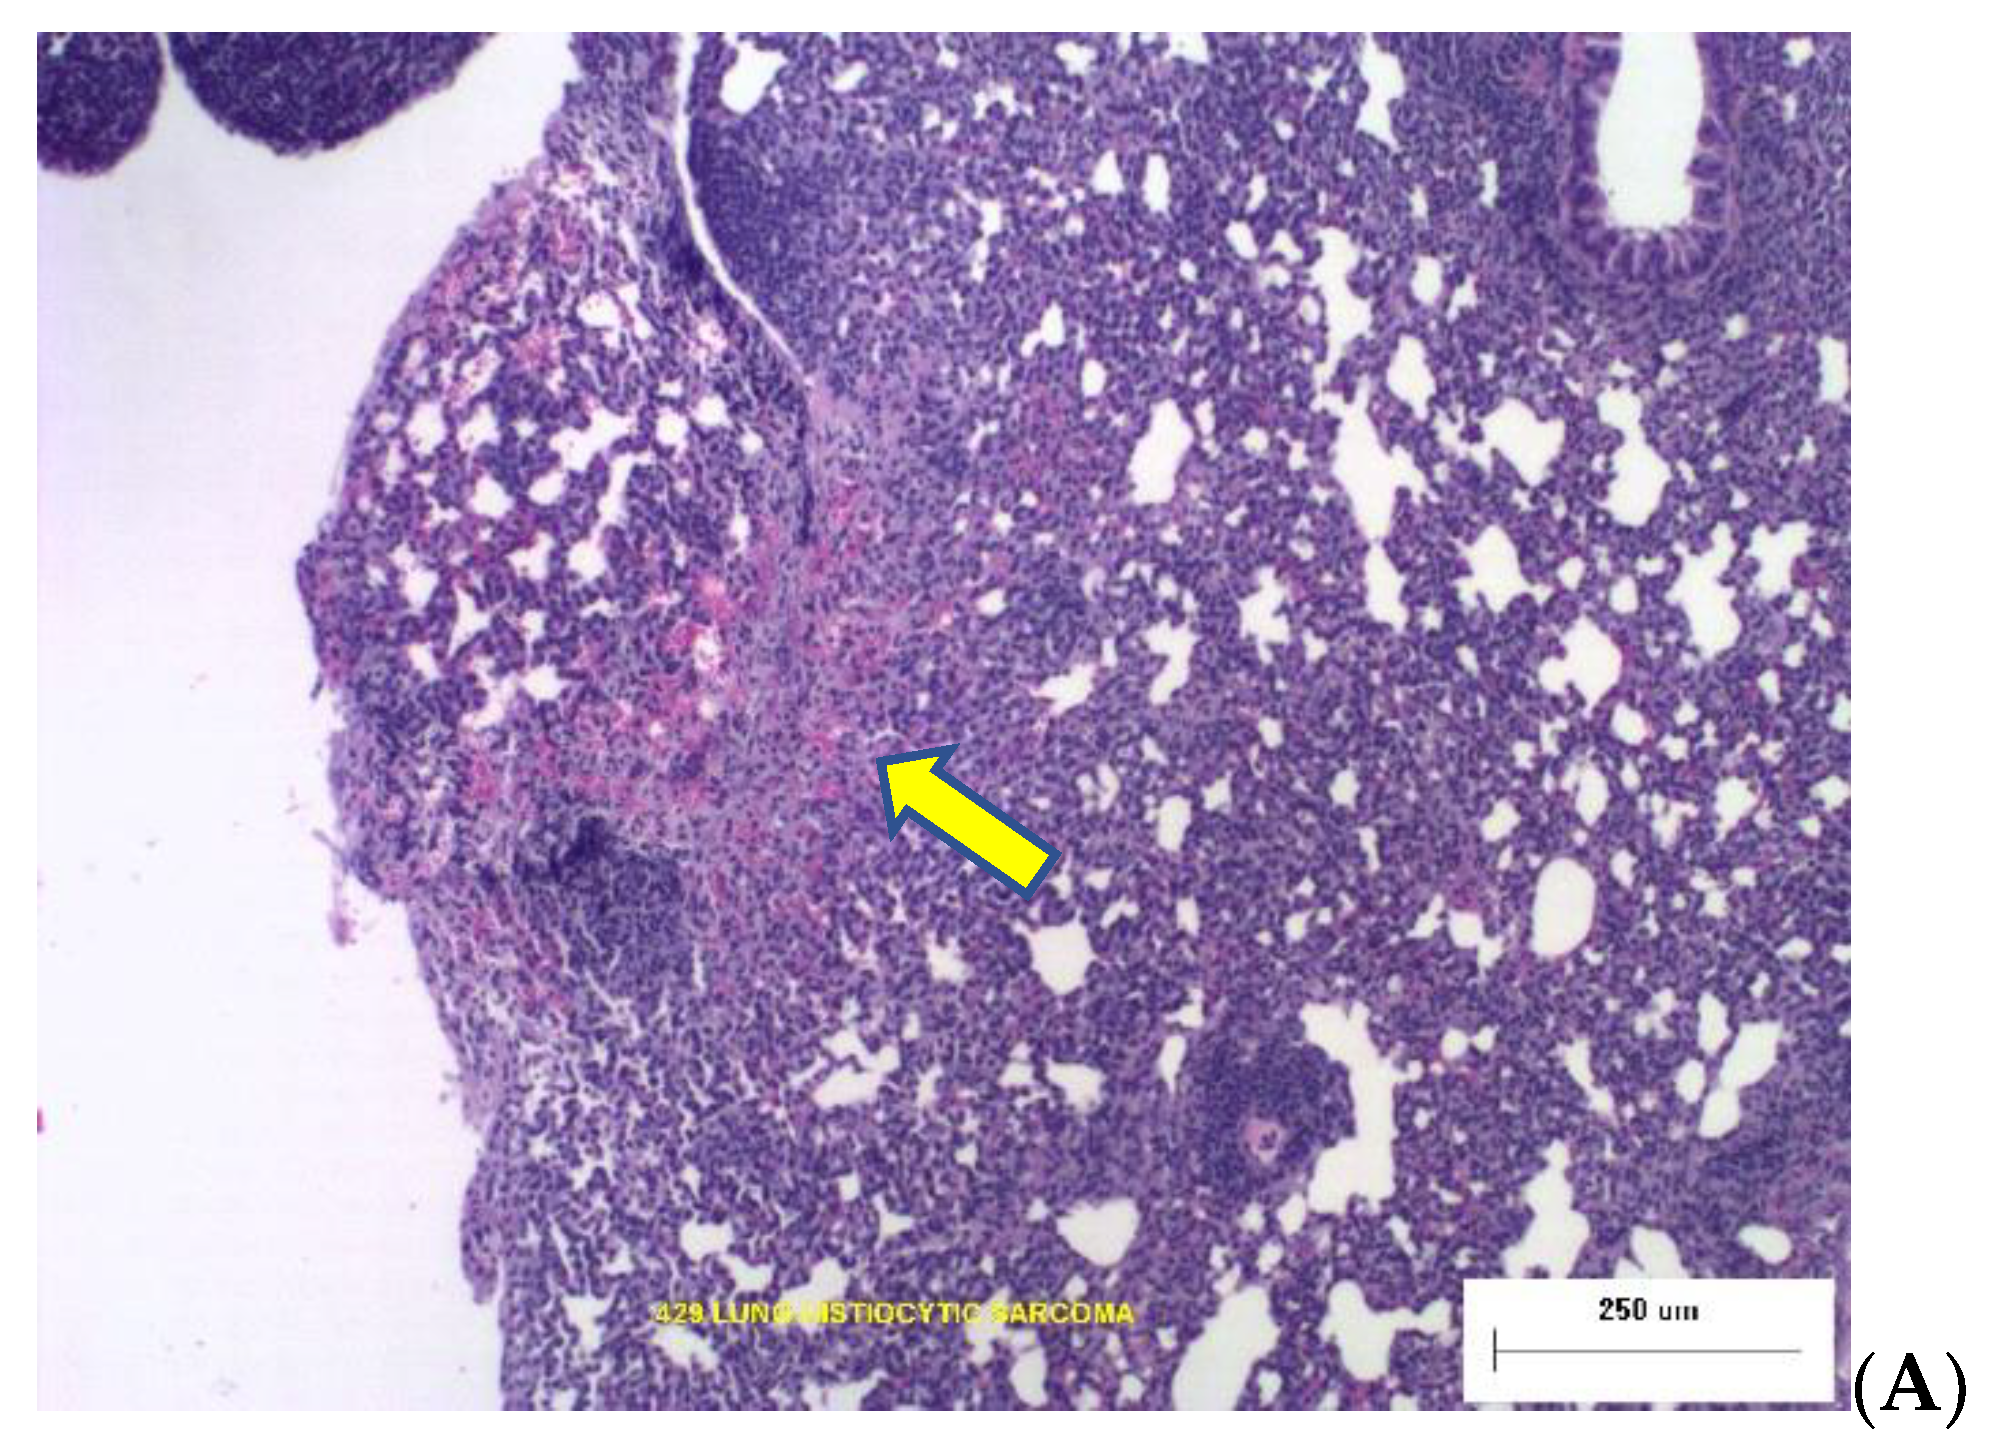

Two photomicrographs are included in Figure 2 illustrating the types of dose-dependent lung pathology observed 16-months after exposure to Silicon ions.

Figure 2. Representative photomicrographs of lung tumor histopathology at necropsy 16 months post irradiation. (A) The yellow arrow points to Broncho-Alveolar Adenoma with adjacent normal tissue from an animal that was irradiated with 0.04 Gy Silicon. (B) Histiocytic Sarcoma in lung tissues from animal exposed to 0.16 Gy Silicon ions.